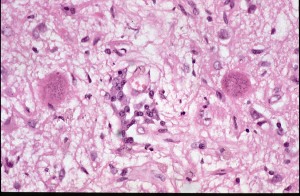

Section from brain of a dog infected with Toxoplasma gondii

This is a low power view of a section from the brain of a dog infected with T.gondii. The dog had a history of fits and convulsions and on necropsy large numbers of T.gondii cysts were found in its brain.

The two pink bodies with darker staining granules are the tissue cyst forms of the parasite and contain large numbers of bradyzoites - the slow growing stage of the parasite. The bradyzoites are the infective stage for the final host - a carnivore and would infect anything that eat the dog.

The dog itself probably became infected through eating meat containing similar tissue cysts. Notice the absence of any cellular reaction around these cysts.